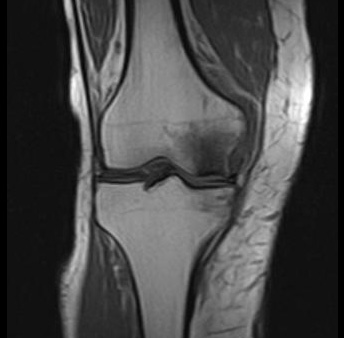

Die Osteonekrose (Knochennekrose) ist das schwierig zu behandelnde Absterben von Knochenzellen im Skelett. Ursachen sind schwer zu ermitteln. Frakturen, Traumata (Gewalteinwirkung) oder Überlastung sind Ursachen. Auch Alkoholismus oder Behandlung mit Kortison bzw. Steroiddoping können Nekrosen im Knochengewebe hervorrufen. Durch die Nekrose verliert der Knochen seine Durchblutung. Er demineralisiert und wird immer anfälliger für eine Fraktur. Eine Osteonekrose unter der Gelenkfläche führt unbehandelt immer zu einer Arthrose.